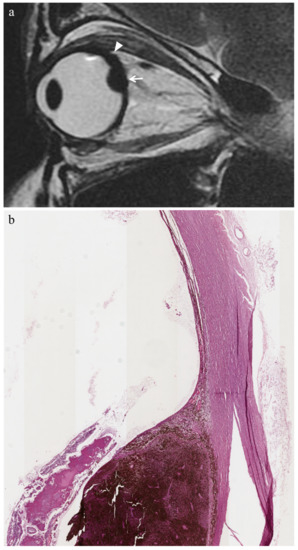

| Uveitis | ![]() High signal | ![]() Low signal | ![]() Enhancement | ![]() High signal |

| Chronic conjunctivitis | - | - | ![]() Enhancement | - |